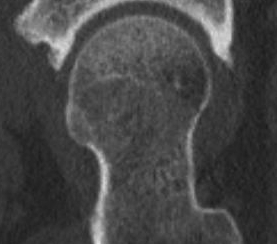

CT

Cam impingement

Alpha angle

Measurement

- centered in the center of the femoral head (best fit circle)

- formed by two lines

- one line center of the femoral neck axis

- a line where the femoral head leaves a best-fit circle

- higher alpha angle with Cam lesion